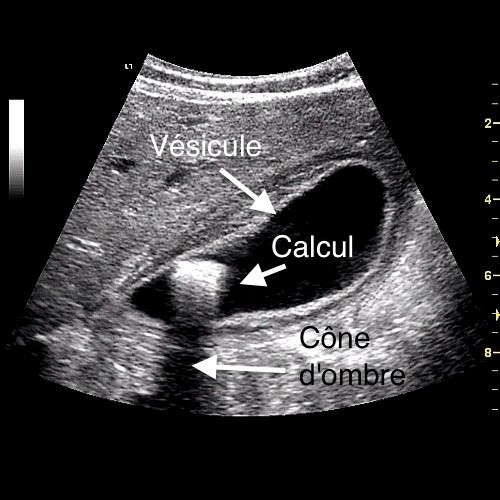

Απαιτείται συχνότερα σε χολολιθίαση : δηλαδή παρουσία λίθων εντός της χοληδόχου κύστεως.

Χολοκυστεκτομή (αφαίρεση χοληδόχου κύστεως)Η διάγνωση συνήθως γίνεται με ένα απλό υπερηχογράφημα.Η χολολιθίαση...